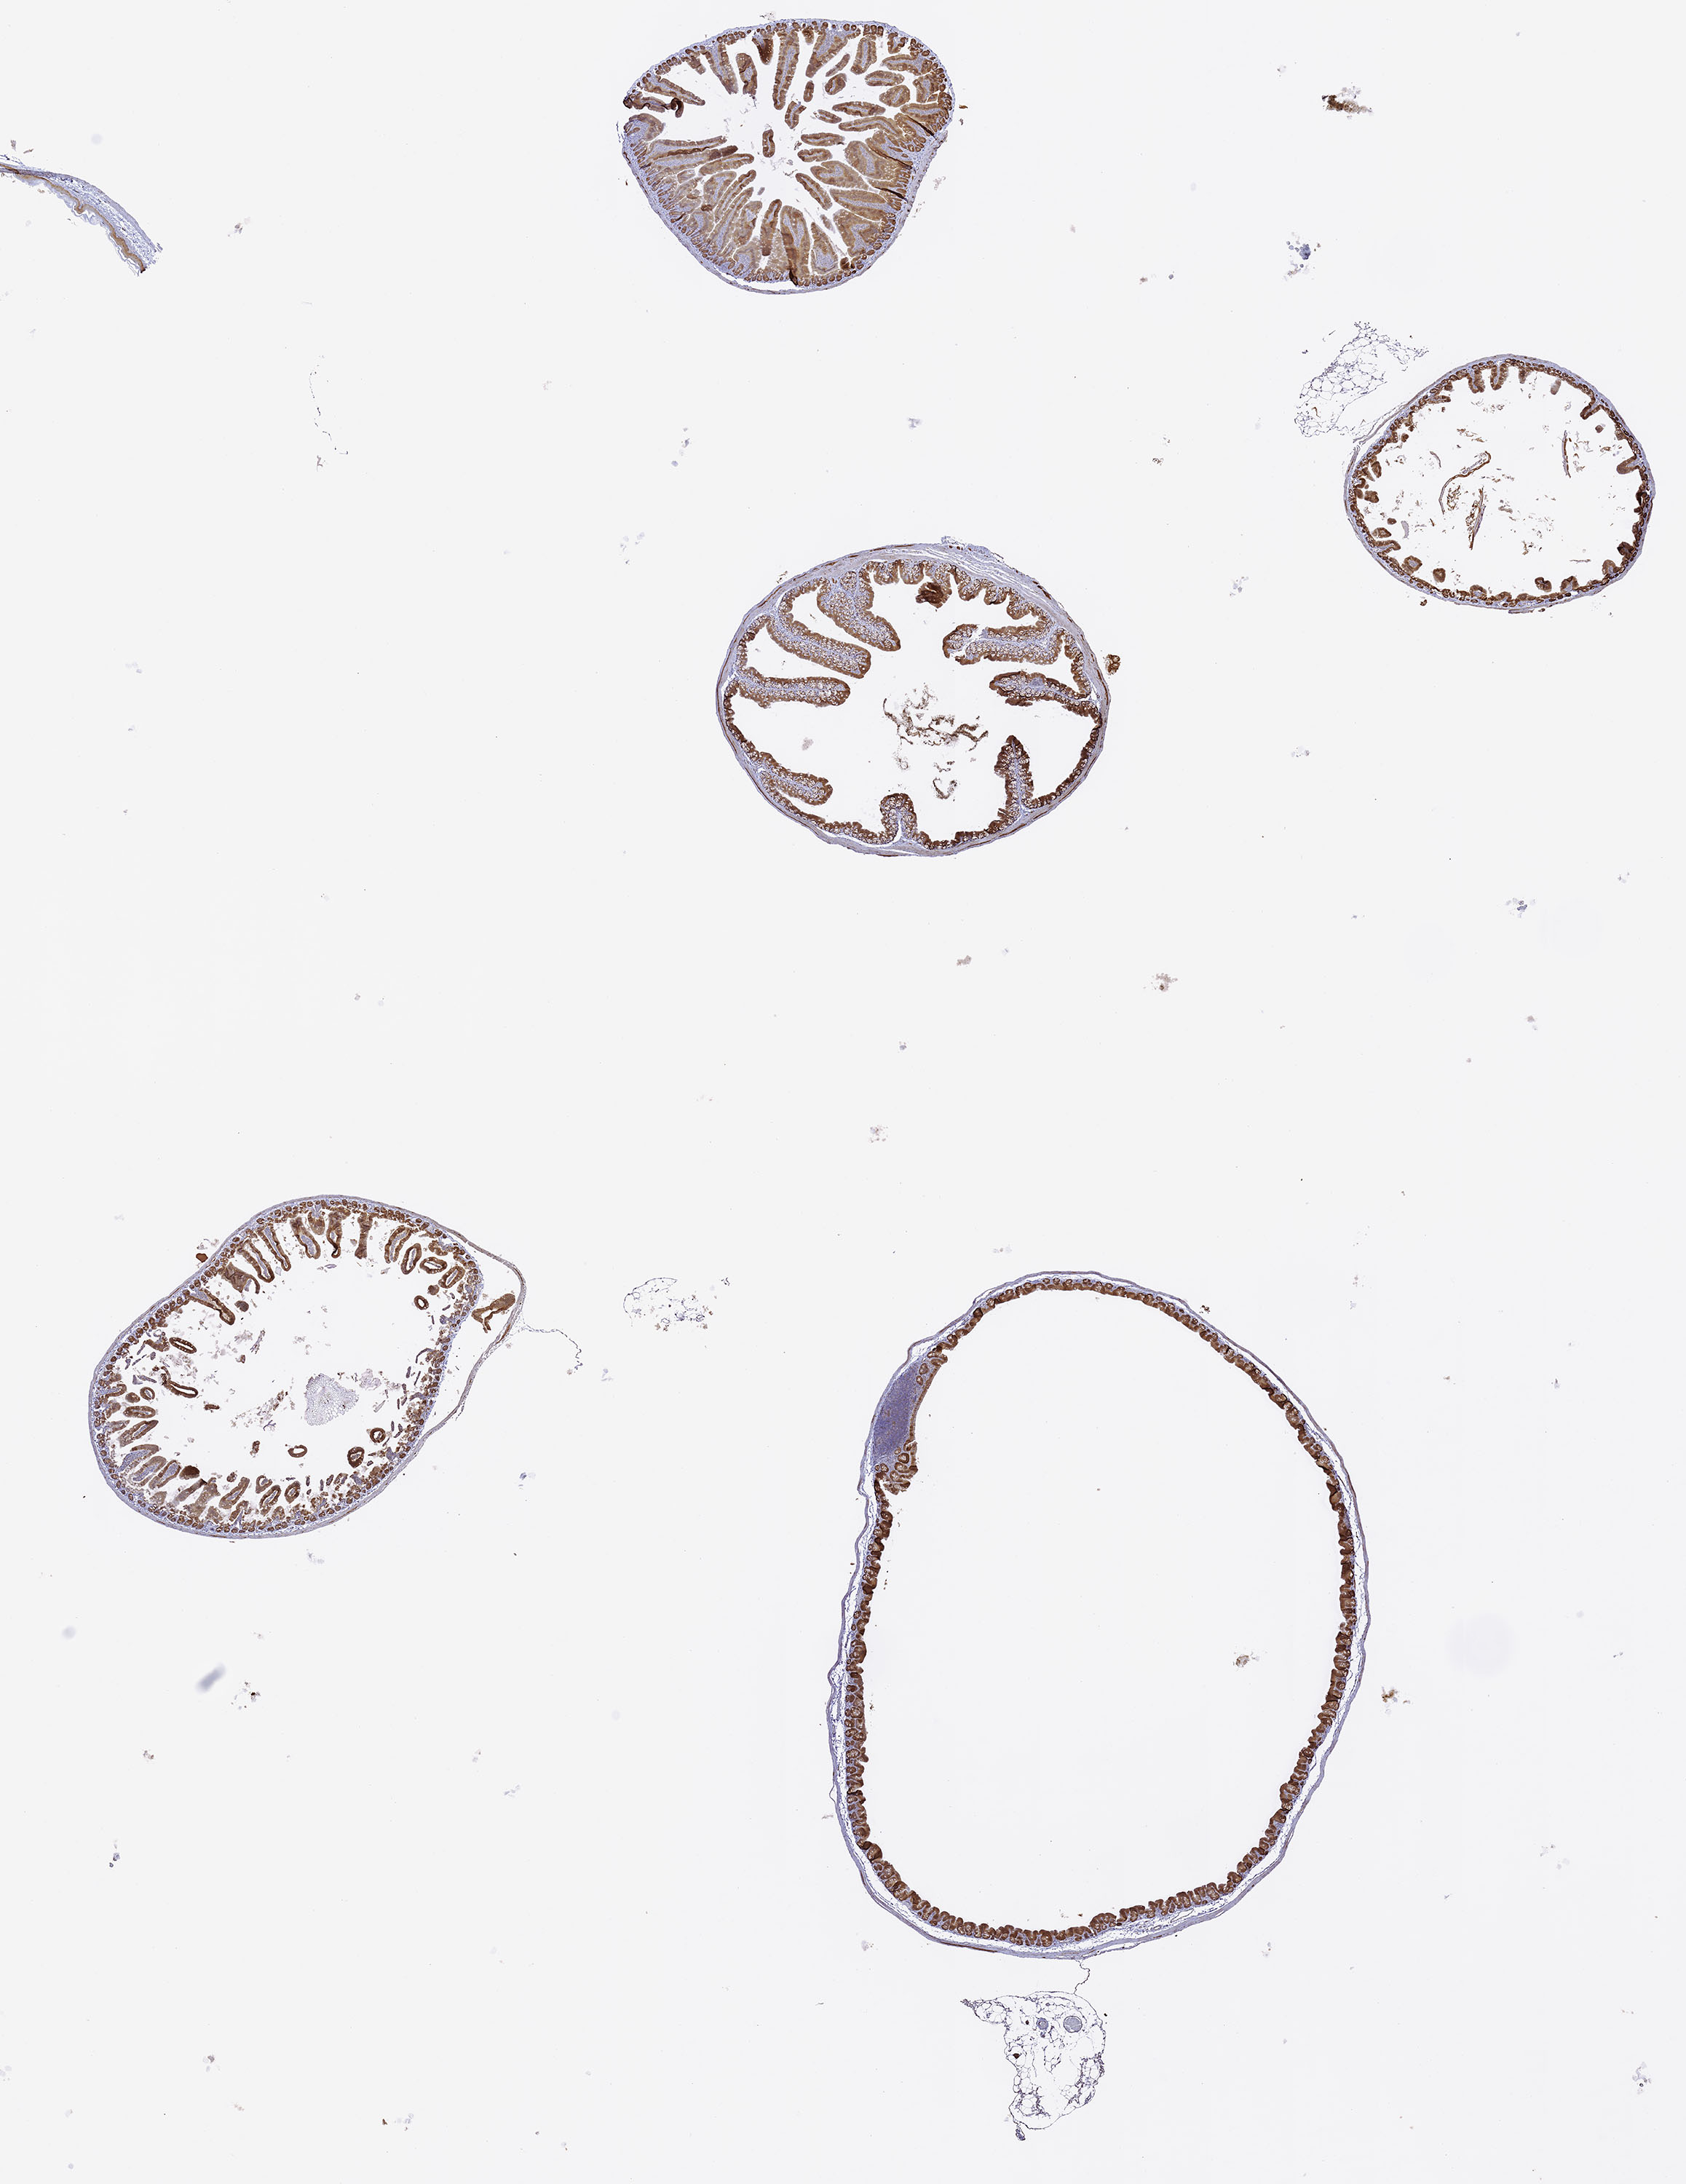

Beta Catenin: Immunoperoxidase staining of normal, formalin-fixed, paraffin-embedded, mouse colon, showing membrane staining of the villi.